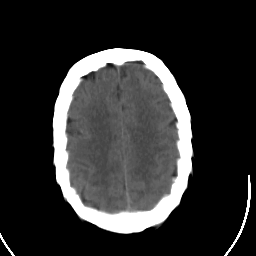

Stroke CT #2 -- Slice #19

[Home][Help][Clinical] Slice 19